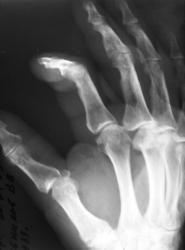

Катенёв Валенти... Дата публикации 01.05.2009, 12:06 Пациент направлен хирургом с диагнозом "перелом". Произвели рентгенографи. Вопрос заключается в том, что данное состояние должно быть обозначено, как "вывих" или "переломовывих"? Пт, 01/05/2009 - 12:46 #1 flagman Не на сайте Был на сайте: 11 лет 5 месяцев назад Зарегистрирован: 05.06.2008 - 20:08 Публикации: 83 а если перелом, вывих. Пт, 01/05/2009 - 12:48 #2 Катенёв Валенти... Не на сайте Был на сайте: 7 лет 4 недели назад Зарегистрирован: 22.03.2008 - 22:15 Публикации: 54876 Спасибо за высказанное мнение. Пт, 01/05/2009 - 13:58 #3 Ермолаев Не на сайте Был на сайте: 8 лет 10 месяцев назад Зарегистрирован: 07.02.2009 - 16:33 Публикации: 670 Валентин Львович! Мое мнение, что имеется вывих и перелом. Два разных костно-травматических изменения с точки зрения патологической анатомии. dok Пт, 01/05/2009 - 14:00 #4 Катенёв Валенти... Не на сайте Был на сайте: 7 лет 4 недели назад Зарегистрирован: 22.03.2008 - 22:15 Публикации: 54876 Спасибо за высказанное мнение. Пт, 01/05/2009 - 14:47 #5 Петрович Не на сайте Был на сайте: 7 лет 2 месяцев назад Зарегистрирован: 22.03.2009 - 01:13 Публикации: 3908 Господа и товарищи! Перелом чего? Неоднозначно всё Сб, 02/05/2009 - 14:39 #6 mihail72 Не на сайте Был на сайте: 11 лет 1 месяц назад Зарегистрирован: 20.06.2008 - 17:49 Публикации: 4 Вывих и мелкооскольчатый перелом основания проксимальной фаланги Сб, 02/05/2009 - 15:53 #7 Петрович Не на сайте Был на сайте: 7 лет 2 месяцев назад Зарегистрирован: 22.03.2009 - 01:13 Публикации: 3908 Показал бы кто пальчиком а) мелкие осколки б) откуда откололись. Кортикальный слой кости и его фрагменты должны быть видны чётко! Неоднозначно всё

Вывих и мелкооскольчатый перелом основания проксимальной фаланги

Показал бы кто пальчиком а) мелкие осколки б) откуда откололись.

Кортикальный слой кости и его фрагменты должны быть видны чётко!